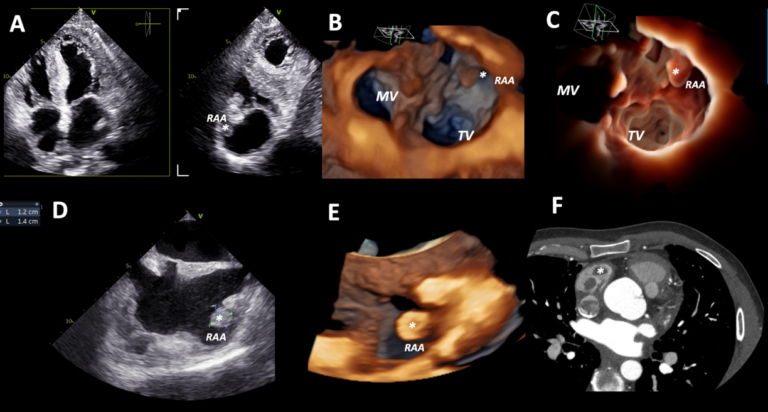

🫀 RISCONTRO OCCASIONALE DI TROMBO IN AURICOLA ATRIALE DESTRA IN UN GIOVANE PAZIENTE CON SCOMPENSO CARDIACO CONGESTIZIO E IN RITMO SINUSALE🫀